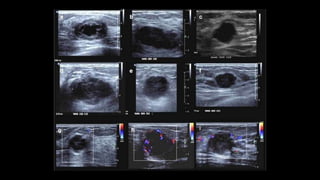

• Ecografía mamaria

• Útil en evaluación de mamas fibrosas

• Determinación de consistencia, tamaño y vascularización periférica

• Permite el estudio guiado por ecografía en pacientes determinadas

• Mal predictor de MCC

ClasificaciónBIRADS-US

• Cat 2: Cicatriz qx estable, colecciones postqx,

ectasia ductal, quistes simples o complicados

múltiples, rotura prótesis, nódulos estables (>2

años o AP de Bx y resultado benigno),

ginecomastia.

• Cat 3: Nódulo sólido ovalado, circunscrito,

paralelo, hipoecogénico sin refuerzo post; quiste

complicado solitario, nódulo sugerente de

necrosis grasa, distorsión arquitectural post qx

• Cat 4a: nódulo oscurecido >75%, sólido y

circunscrito; quiste complicado solitario

palpable, probable absceso

• Cat 4b: asimetría en desarrollo, nódulo sólido de

margen indistinto

• Cat 4c: nódulo nuevo irregular, margen

indistinto